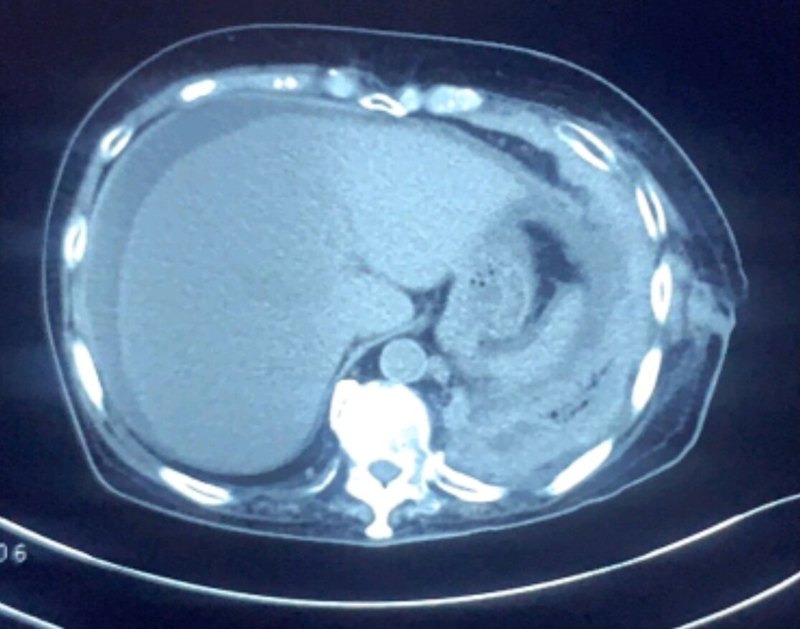

劉懿博士說肺癌(八一五三)胸膜局部增厚多久排除惡性胸膜間皮瘤

有一位家住天津市河東區(qū)的女士兩個月前在當?shù)蒯t(yī)院拍了一個胸部CT,這兩天大仔細看了一下自己的胸部CT報告,里面寫著有雙側胸膜局部增厚。她不明白這種描述代表著什么,上網搜了一下,看到有的文章寫的胸膜增厚有可能是惡性胸膜間皮瘤。她又了解了一下惡性胸膜間皮瘤,讓她非常害怕,因為這種疾病惡性程度比較高,治療效果不好。她想自己才四十七歲,有沒有可能得這種病呢?于是她在線上問診平臺聯(lián)系到我,把自己的電子圖像發(fā)給我看,想聽聽我的分析。我反復閱讀她的電子圖像,目前不考慮惡性胸膜間皮瘤,可以先觀察一下。她問我要觀察多久才可以排除這種疾???每個醫(yī)生的經驗不同,對這種疾病的看法也不一樣,我自己的經驗如果三年沒有變化,就可以排除這種疾病了。惡性胸膜間皮瘤的早期表現(xiàn)確實就是從胸膜增厚開始的,但不是所有的胸膜增厚都是惡性胸膜間皮瘤,這二者不是劃等號的。